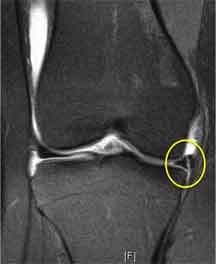

So when a patient has a meniscal tear a surgeon wants to determine “what shape is the tear and where about is it occurring?”, one can tell a great deal from the MRI scan, which will tell if the tear is longitudinal (like in the MRI scan on the right - circled in yellow), radial or a horizontal cleavage, and one can see from where the tear is on the MRI scan how peripheral it is and therefore how likely it is that it will be reparable. The other thing of course is the history (the patient’s story).